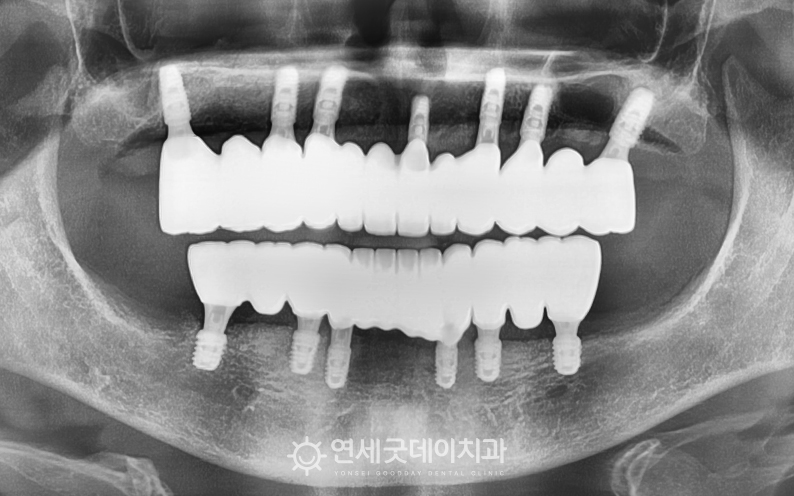

전체임플란트 및 상악동수술 치료전후 (50대)

전체임플란트 치료를 마친 후 엑스레이 모습입니다. 꼭 필요한 위치에만 임플란트를 식립한 뒤

전체임플란트 식립 이후 보철 제작 단계에서도 또한, 환자분의 니즈를 반영하여 치아 모양과 길이,